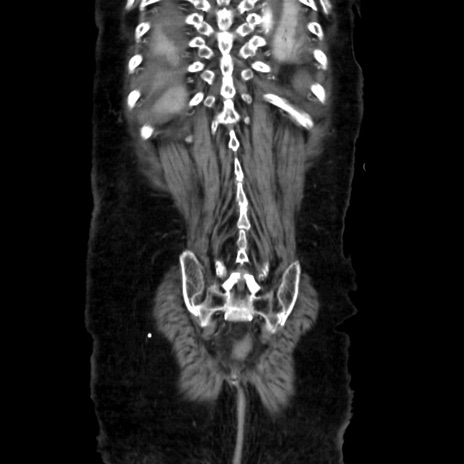

矢状断像